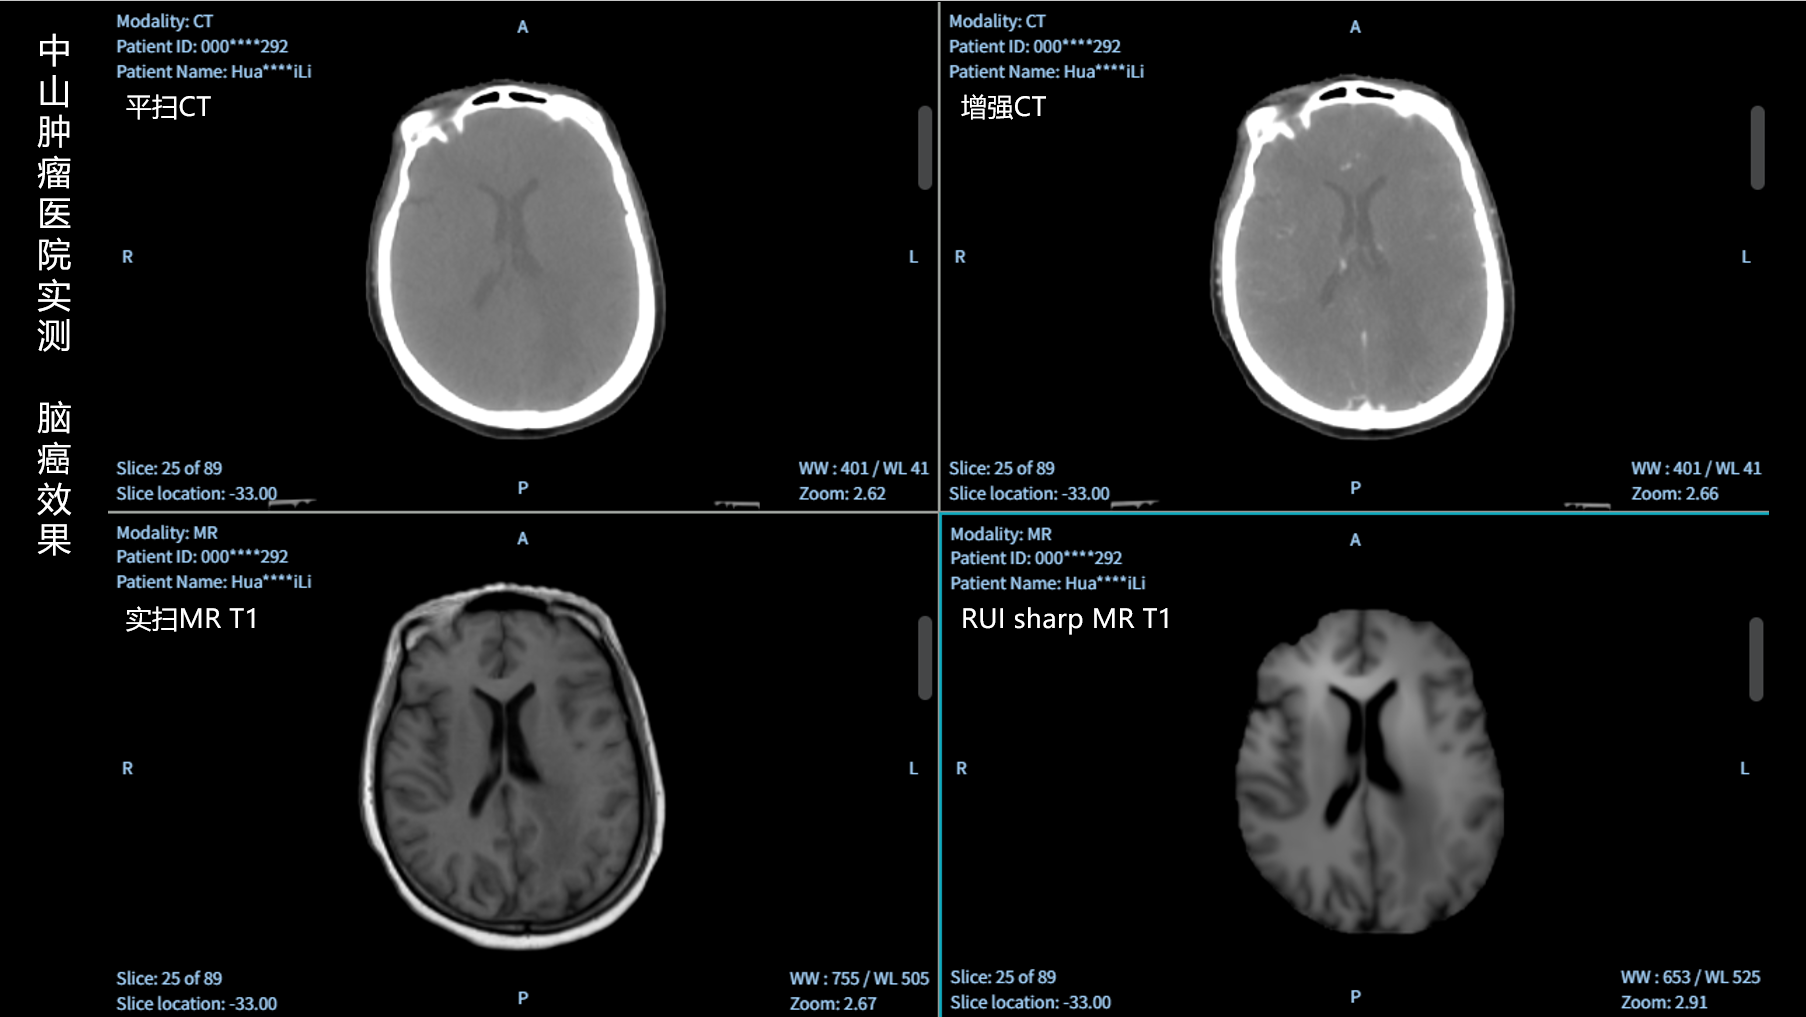

RUI sharp H(锐影)可在不依赖MRI的前提下,显著提升头部CT图像的软组织分辨率,为临床提供更高质量的辅助信息,尤其适用于MRI资源受限或较难配准的头颈部放疗感兴趣区勾画场景。

可大幅提高头部CT影像软组织分辨率,使肿瘤和周边器官显示更清晰,为放疗靶区勾画提供参考。

无需图像配准,CT和锐影图像同源,可匹配、叠加、"淡入淡出"显示。